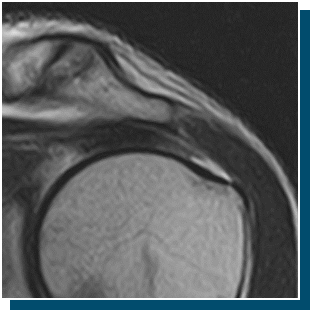

治療の副作⽤

ご⾃⾝の脂肪細胞を使⽤するため、アレルギー反応や拒否反応が起こる可能性は⾮常に低いとされています。

ただし、注射による処置である以上、感染などのリスクを完全にゼロにすることはできません。

こうしたリスクを最⼩限に抑えるため、衛⽣管理や感染予防対策には最⼤限の配慮を⾏っております。

治療前には、詳細なご説明をいたしますので、ご不安な点がありましたらどのようなことでもご質問ください。

万が⼀、治療に対して不安が拭えない場合には、無理におすすめすることはございません。

ご希望やお⾝体の状態に合わせて、他の治療法をご提案することも可能です。